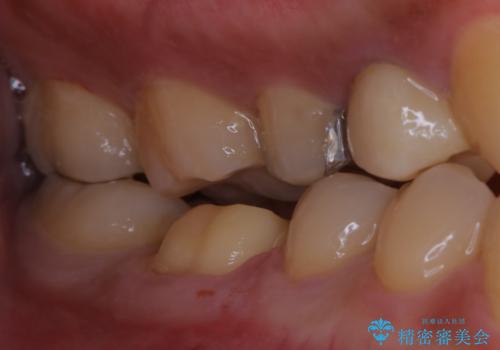

- セラミックへのやり替えを希望された患者様です。

日常的に食いしばる癖があり、歯の表面にはエナメルクラック(歯の表面にできる細かい破折線)も複数認められたため、セラミッククラウンによる治療をご提案しました。